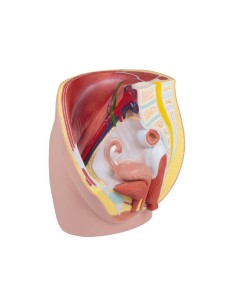

3B Modèle scientifique et gynécologique pour l'entretien avec les patientes P53

3B Scientific. Kit d'enseignement, système de reproduction femelle W40214